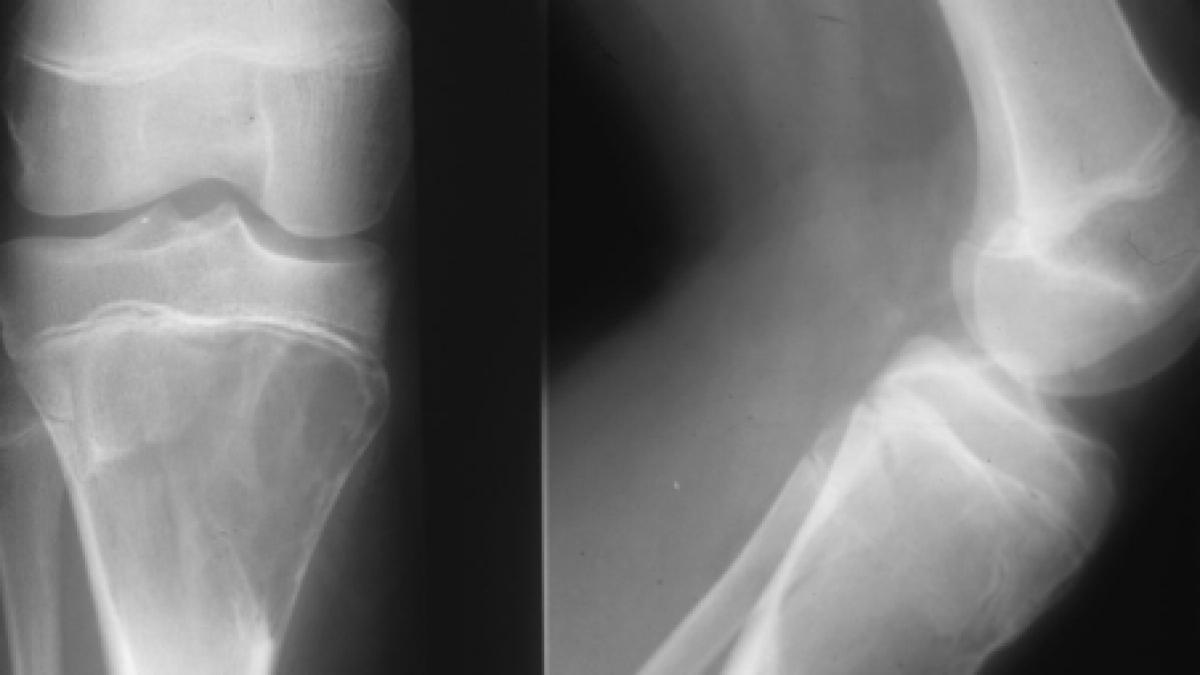

Boala oaselor de sticla. Comentarii boala oaselor de sticla sau osteogeneza imperfecta este o boala ereditara rara a tesutului conjunctiv caracterizata prin fragilitate osoasa. Cele mai importante caracteristici ale bolii observabile clinic sunt. Boala este o forma de osteogeneza imperfecta adica tesutul osos este in acest caz de o calitate proasta din cauza unei anomalii de structura a colagenului. Fetița cu oase de sticlă la numai șapte anișori alexia elena se confruntă cu o boală gravă care o împiedică uneori să facă lucruri considerate banale de alți copii de vârsta ei.

Alexia trebuie să aibă. Boala oaselor de sticla aceasta boala este ereditara caracterizata printr o fragilitate a oaselor. Iniţial s a numit boala oamenilor de sticlă sau boala oaselor de sticlă. O persoană cu această patologie va fi afectată toată viaţa patologia neavând tratament.

Boala oaselor de sticla sau osteogenoza imperfecta asa cum se numeste ea in limbaj de specialitate este incadrata in categoria patologiilor ereditare rare cu o incidenta de circa 1 la15 000 20 000 de cazuri influentand enorm viata celor afectati. Osteogeneza imperfectă este o boală ereditară rară a ţesutului conjunctiv caracterizată prin fragilitate osoasă. Din cei zece copii care se nasc în fiecare an în ţara noastră cu osteogeneză imperfectă trei prezintă formă gravă şase au formă severă iar unul are o formă uşoară. Boala oaselor de sticla din dictionar termeni.

Aceasta boala este ereditara caracterizata printr o fragilitate a oaselor.